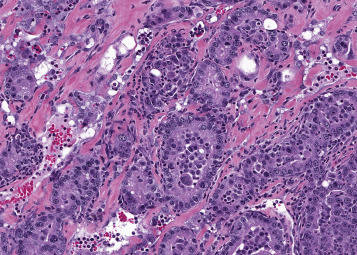

Alveolar/bronchiolar carcinomas are often poorly circumscribed (Figure 23.30, Figure 23.31 ). However, rapidly growing neoplasms may cause compression of the surrounding parenchyma and appear moderately well demarcated (Figure 23.32, Figure 23.33 ). The carcinomas may invade airways (Figure 23.34, Figure 23.35 ), pleura, or vessels and metastasize to regional lymph nodes, liver, kidney, heart, or other organs. Hallmarks of alveolar/bronchiolar carcinomas are their heterogeneous growth patterns and cellular pleomophism (Figure 23.36, Figure 23.37 ). Morphologic growth patterns vary from glandular, papillary, solid, to a mixture of these patterns. Well-differentiated carcinomas with a papillary pattern are difficult to distinguish from adenomas. Stratification of the neoplastic epithelium, solid areas of growth, cellular pleomorphism, and atypia or anaplastic cells associated with a scirrhous reaction and local invasion are indications of malignancy (Figure 23.34, Figure 23.35, Figure 23.36, Figure 23.37). Alveolar or glandular patterns of growth are usually observed only when there is a prominent connective tissue component or scirrhous reaction. Scirrhous reactions are not commonly seen in spontaneous alveolar/bronchiolar carcinomas, but occur in some carcinomas induced by exposure to particulate chemicals such as asbestos, silica, gallium arsenide, cobalt sulfate heptahydrate, cobalt metal, and other particulate chemicals. In some small neoplasms, the scirrhous reaction may be so pronounced that the neoplasm appears to arise within an area of fibrosis. Neoplastic cells within a carcinoma may be pleomorphic, and particularly anaplastic cells may be spindle shaped (Figure 23.38 ). Squamous differentiation is observed in some carcinomas and may be quite prominent (Figure 23.39 ). However, the diagnosis of squamous cell carcinoma is restricted to neoplasms that consist predominantly of squamous cells. Otherwise, neoplasms with squamous differentiation are classified as alveolar/bronchiolar carcinomas on the assumption that they are more anaplastic variants of alveolar/bronchiolar carcinomas. Neoplastic cells may also differentiate into a mucinous cell type; however, such differentiation is rare. Metastases from spontaneous alveolar/bronchiolar’ carcinomas are not commonly observed but may be more frequent with induced carcinomas. The metastatic lesions exhibit a papillary or glandular pattern of growth.

Figure 23.36.

Alveolar/bronchiolar carcinoma with a heterogeneous growth pattern and a scirrhous component (asterisk).

Figure 23.37.

Higher magnification of Fig. 23.36. Note heterogeneous growth and anaplastic, pleomorphic cells interspersed with irregular bands of fibrous tissue.